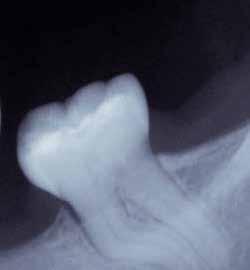

1. ábra: A 15-ös foggyökér meziális felszíne mellett látható radiolucens elváltozás, illetve a felvételen látható a korábban behelyezett gyökértömés, a parapulpális csap segítségével elhorgonyzott csonkfelépítés és a fogat borító cirkonkorona. –2. ábra: A saggitalis irányú CBCT-metszeten jól megfigyelhető az állcsontgerincet elérő radiolucens elváltozás. – 3. ábra: Az axiális irányú CBCT-metszeten egyértelműen látható a kezeletlen palatinális gyökércsatorna, valamint a radiolucens elváltozás mezio-disztális kiterjedése is jól megítélhető. – 4. ábra: A palatinális gyökércsatorna szelektív endodonciai kezelése során először gyógyszeres zárás került behelyezésre. – 5. ábra: A gyógyszeres zárás során alkalmazott kalcium-hidroxid alapú paszta a szulkuszon keresztül a szájüregbe extrudálódott. – 6. ábra: A gyökértömő anyag a középső és apikális gyökéri harmad határán lévő laterális csatornán keresztül a periapikális térbe extrudálódott. 7. ábra: A kezelések befejezését követően 4 évvel készült röntgenfelvételen jól látható a csontállomány gyógyulása és a fiziológiás gyökérhártyarés újbóli kialakulása. –8. ábra: A peroperatív CBCT-felvétel alapján készített koronális irányú metszeten jól látható a gyökércsúcs körül lévő periapikális felritkulás. – 9. ábra: A kezelések befejezése után 4 évvel készített CBCT-felvételen a gyulladásos lézió teljes megszűnése észlelhető.

A CBCT-készülékek endodonciai alkalmazásának talán az az egyik legnagyobb előnye, hogy így olyan anatómiai struktúrák is láthatóvá válnak, amelyeket egyébként nem tudnánk detektálni panoráma, cephalo, vagy periapicalis felvételek segítségével. Mivel a CBCT-felvételek kiértékelése számítógép segítségével történik, így a felvételek vizsgálata során lehetőségünk van az adott területet több nézőpontból és több síkban is megvizsgálni. 2015 októberében egy korábban a rendelőnkben kezelt 55 éves férfi páciens azzal a céllal kereste fel ismét a rendelőnket, hogy másodvéleményt kérjen egy jobb felső kvadránsban található fogával kapcsolatban. Egy másik rendelőben történő vizsgálat során a panaszos fog törését vélelmezték és a fog eltávolítását javasolták, illetve arról is beszámolt, hogy az elmúlt hét során ezen a területen egy puha duzzanat is kialakult. A klinikai vizsgálat során a jobb felső első és második kisőrlő között (14–15) egy fluktuáló duzzanatot észleltünk az áthajlásban. Az 15-ös fog mesialis oldalán 12 mm mély tasakot szondáztunk. A páciens által hozott periapicalis felvételen a 15-ös fog gyökércsúcsának mesialis részén egy nagy kiterjedésű radiolucens elváltozás volt észlelhető (1. ábra). A saggitális síkban vizsgált CBCT-felvételen (Carestream CS 9000, Carestream Dental) a lézió valódi kiterjedése is láthatóvá vált (2. ábra). A megelőző endodonciai kezelések során csupán a bukkális csatorna került detektálásra és gyökértöméssel való ellátásra. Az axiális irányú CBCT-szeleteken egyértelműen látható volt az ellátatlan palatinális gyökércsatorna (3. ábra)

Először kalcium-hidroxid alapú ideglenes gyógyszeres zárás került a palatinális csatornába (UltraCal XS, Ultradent Products; 4–5. ábra), amelyet 6 hét után a végleges gyökértömés elkészítése előtt eltávolítottunk. A gyökértömés elkészítése során meleg vertikális kondenzációs technikát alkalmaztunk. Radiológiai felvételen megfigyelhető volt, hogy a gyökértömő anyag egy laterális csatornán keresztül kis mennyiségben a periapicalis térbe extrudálódott (6. ábra). A 4 évvel később készített kontrollfelvételeken a lézió gyógyulása volt megfigyelhető (7–9. ábra). A vizsgálati eredmények és a kezelés kimenetele egyértelműen igazolta, hogy nem gyökérfraktúrával álltunk szemben, tehát a kezdeti diagnózis tévesnek bizonyult. Ez is azt erősíti, hogy korlátozott mennyiségben rendelkezésre álló adatok alapján nem lehet pontos diagnózist felállítani. Manapság szinte elengedhetetlen a CBCT-felvételek endodonciai beavatkozások során történő használata, feltéve, ha ezek elkészítése során az ALARA elv (as low as reasonably achievable) betartásra kerül.